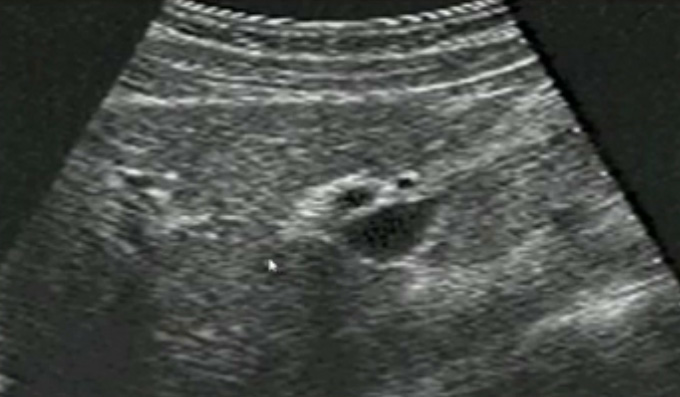

一、正常膽囊超聲圖像有的時候經常發現檢查不到膽囊,其實有幾種可能性,檢查人員的技術不過關沒發現膽囊,就要找上級醫生會診,如果還是沒找到的話就不是技術問題。結石或腫瘤充滿膽囊,使其液腔消失,慢性膽囊炎使得膽囊萎縮或膽囊壁肥厚而囊腔消失患者已進食,膽囊處于膽汁排空的狀態,膽囊先天性過小或缺失;膽囊位置極端異常(可能很低或位于左側)膽囊切除術后(注意詢問病史)。